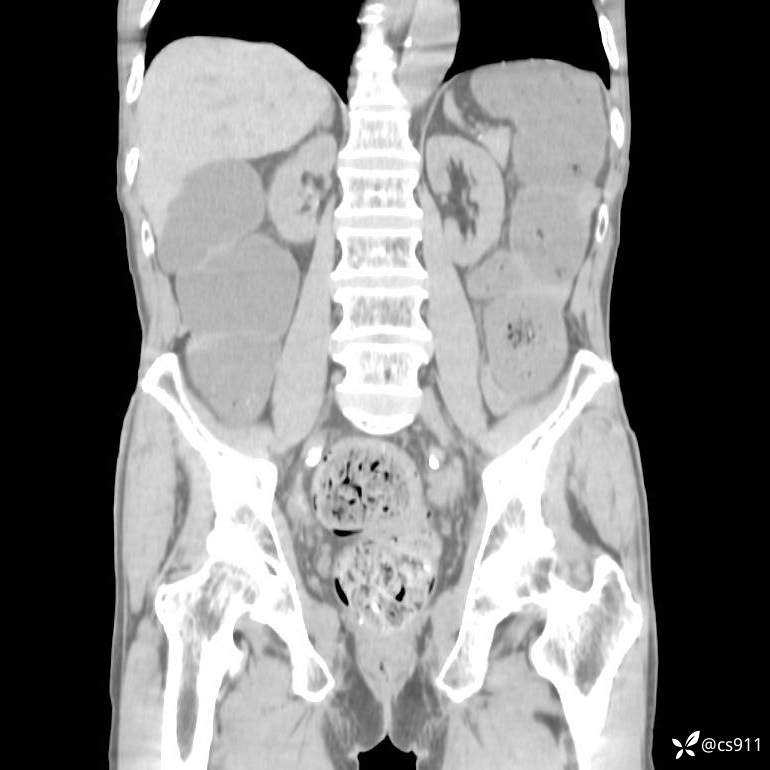

急腹症之急诊CT,原因?答案公布

男,77岁,腹痛、腹胀伴恶心呕吐1天。呕吐胃内容物,非喷射性呕吐,有咖啡色样胃内容物,诉有胃穿孔病史。查体:全腹平,下腹部压痛,全腹无反跳痛,叩诊呈浊音,移动性浊音阴性,肠鸣音减弱,1-2次/分。肛检:直肠未扪及明显肿物,可触及大量粪块。

T 36.6℃ P 80次/分 R 26次/分 BP 100/60mmHg

白细胞(WBC) H 14.55 10e9/L 4-10

中性粒细胞百分率(NEUT%) H 85.7 % 40-75

血淀粉酶(AMY) HH 1859 U/L 35-135

癌胚抗原(CEA) H 27.44 ng/ml 0-5

呕吐物 潜血试验 * 阳性 阴性

患者轮椅入室检查神志清楚, 能配合摆位和呼吸